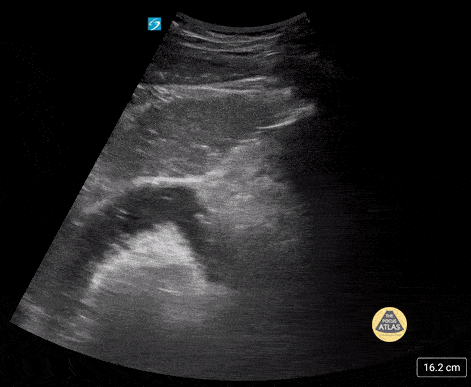

17 yo male with history of abdominal surgeries (g-tube and fundoplication) and chronic constipation who comes in with lower abdominal pain. POCUS shows stool to and fro (tanga sign). Contributor: Paul Khalil, MD Nicklaus Children's Hospital @khalil3paul